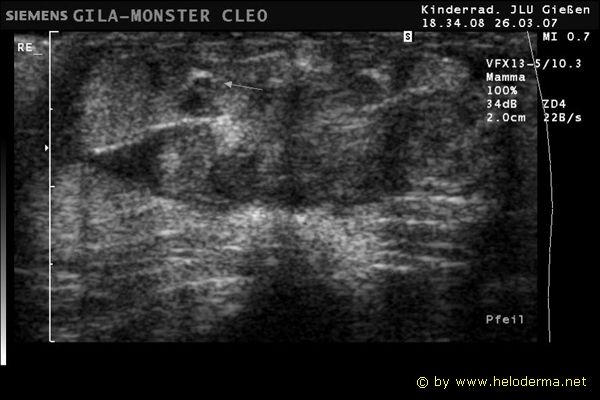

Échographie de la racine de la queue d'un mâle adulte Heloderma suspectum.

Les hémipénis ainsi que les poches hémipéniennes sont visibles. Ils se présentent comme une paire de structures d'environ 2 cm de long qui se différencient du reste de la structure de la queue (Biblio.35).

Échographie de la racine de la  queue d’un mâle, représentation des poches hémipéniennes

Échographie de la racine de la queue d’un mâle avec des structures de longueur Échographie de la racine de la queue Échographie de la racine de la queue d’un mâle avec des structures de longueur

Échographie de la racine de la  queue d’un mâle, représentation des poches hémipéniennes Échographie de la racine de la queue d’un mâle avec des structures de longueur Échographie de la racine de la  queue d’un mâle, représentation des poches hémipéniennes

L'imagerie ultrason a été effectuée dans le service de Radiologie Infantile (Dir. Prof. Gerhard Alzen) du Centre Médical de Radiologie de l'Hôpital Universitaire de Giessen, Feulgenstrasse 12, 35358 Giessen.

Examens réalisés avec un échographe (de fabrication Siemens) avec un transducteur linéaire de 7,5 MHz.

Pour l'examen de la racine de la queue on utilisa un transducteur linéaire de 7,2 – 12,0 MHz